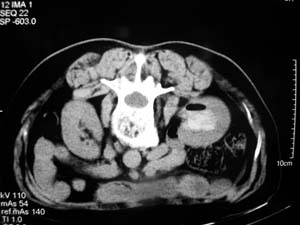

我们主要在ct引导下进行各种囊肿的穿刺引流,对于肾囊肿治疗的较多.穿刺成功后尽量抽尽囊液并且记录数量,抽尽后注入造影剂看看是否与尿路相通,然后用1/4的比例注入无水酒精进行硬化.跟踪观察治愈率达98%以上.